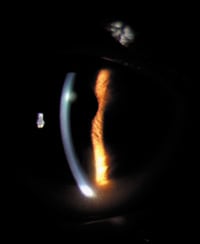

Figure 1. A corneal infiltrate resulting from GP-induced VLK. |

Slit lamp biomicroscopy OD revealed faint midperipheral corneal scars at 10 o'clock and four o'clock from previous corneal ulcers. The left conjunctiva had moderate injection adjacent to the nasal limbus with overlying fluorescein stain. A corneal infiltrate was present from eight o'clock to 10 o'clock with elevated, staining, hyperplastic epithelium and vascularization throughout (Figure 1).

We diagnosed vascularized limbal keratitis (VLK) OS. Grohe and Lebow first described VLK in 1989. It's a peripheral corneal disorder induced by GP daily or extended wear and associated with large overall lens diameters, minimal edge lift designs and steep base curve-to-cornea fitting relationships. Signs and symptoms include peripheral corneal desiccation, infiltration and inflammation as well as surface erosion, discomfort and decreased wearing time.

Case 1, Visit 2 Our patient cancelled her first appointment and returned two weeks later, reporting less redness and no irritation OS. The large corneal infiltrate showed significant improvement, was mildly elevated, had trace staining and was vascularized throughout. We noted a small intracorneal hemorrhage at this visit (Figure 2). We instructed the patient to continue the ocular lubricant and to discontinue the steroid. We advised her to return in one week for a comprehensive examination and contact lens fitting.

We also billed external ocular photography, 92285 to show resolution of the VLK and to document the intracorneal hemorrhage.